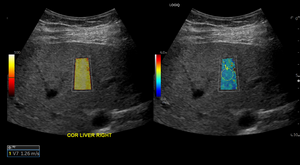

In the retrospective study, the researchers compared liver stiffness of patients with a history of COVID-19 infection to two control groups. All patients underwent ultrasound shear wave elastography between 2019 and 2022 at Massachusetts General Hospital. Shear wave elastography is a specialized technique that uses sound waves to measure the stiffness of tissue.